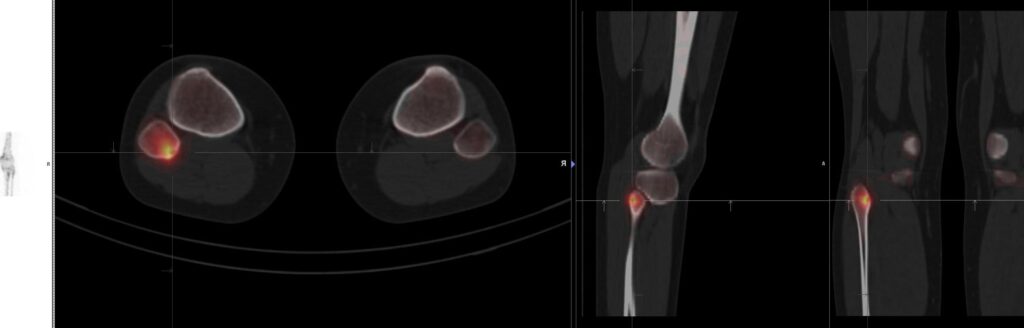

La scintigraphie osseuse est une technique d’imagerie médicale nucléaire incontournable dans l’évaluation et le diagnostic de nombreuses pathologies squelettiques. En particulier, lorsqu’il s’agit de l’arthrose, une affection dégénérative touchant les articulations, cette modalité d’examen peut apporter des informations précieuses. La radionucléide utilisée en scintigraphie osseuse se fixe sur les zones où le métabolisme osseux est intensifié, ce qui permet de mettre en évidence les régions atteintes par l’arthrose avec une grande sensibilité. Cette méthode d’imagerie se distingue par son caractère non invasif et sa capacité à réaliser une évaluation globale du squelette, offrant ainsi une vue d’ensemble qui peut échapper à d’autres techniques plus localisées comme la radiographie ou l’IRM (Imagerie par Résonance Magnétique). En outre, la scintigraphie osseuse permet de suivre l’évolution de l’arthrose ou d’autres maladies osseuses, facilitant ainsi la prise en charge thérapeutique adaptée. Cet examen, qui requiert une expertise soignée pour son interprétation, repose sur l’utilisation de traceurs marqués par des éléments radioactifs, tels que le technétium-99m, assurant ainsi la production d’images scintigraphiques de haute qualité.

L’examen se déroule en deux étapes principales : tout d’abord, un radiotraceur (généralement du technétium-99m) est injecté dans la veine du patient. Ce produit se fixe sur les zones osseuses ayant une activité métabolique élevée, typiques des zones touchées par l’arthrose. Après une période d’attente nécessaire à la fixation du radiotraceur, le patient est placé sous une caméra gamma qui va détecter la radioactivité émise et créer une image des os.

L’interprétation des résultats de la scintigraphie doit être effectuée par un spécialiste en médecine nucléaire, en prenant en compte le contexte clinique du patient. Des zones d’intenses fixations peuvent indiquer des régions fortement touchées par l’arthrose. Sur la base de ces résultats, le traitement peut être adapté et mieux ciblé.

La scintigraphie osseuse est une technique d’imagerie médicale qui permet de détecter les changements dans le métabolisme osseux. Elle utilise des traceurs radioactifs, lesquels sont absorbés par le tissu osseux en fonction de son activité. En cas d’arthrose, des modifications du cartilage et de l’os adjacents peuvent induire une augmentation de l’activité osseuse. La scintigraphie peut donc révéler ces zones d’activité accrue, appelées « hot spots ». Ces informations peuvent aider à confirmer le diagnostic d’arthrose, à évaluer son étendue et à suivre la progression de la maladie.